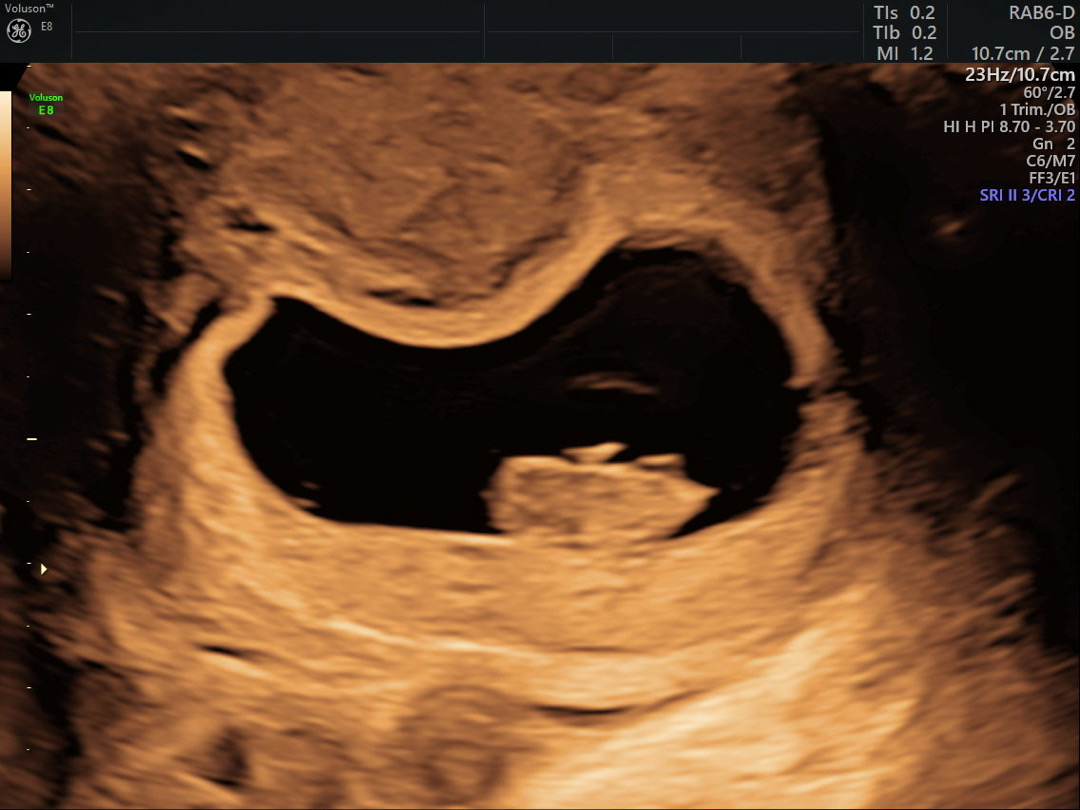

8주1일차 첫 초음파 확인했어요 🤩

해외살아서 초음파도 거의 십만원내고 처음 받았어요. 그렇게 감격일수가없었네요 ❤️ 근데 젤리곰은 안보이고 너무 모양이 특이해요 😂 12주때 보면 좀더 사람처럼 보이겠죠?